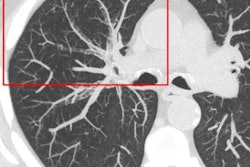

The group led by Luuk Oostveen of Radboud University Medical Center in Nijmegen compared the technical performances of the Aquilion Precision ultrahigh-resolution CT scanner (Canon Medical Systems) and the Aquilion One Genesis MDCT system (Canon) using standard procedures and phantoms. The researchers found that the Precision scanner's high-resolution and superhigh-resolution mode resulted in double the spatial resolution, but with an approximate 23% increase in dose required to achieve the same low-contrast detectability.

"With abdominal settings, [ultrahigh-resolution CT] needs higher dose for the same low-contrast detectability as MDCT, but dose is still below achievable levels as defined by current diagnostic reference levels," the authors wrote.